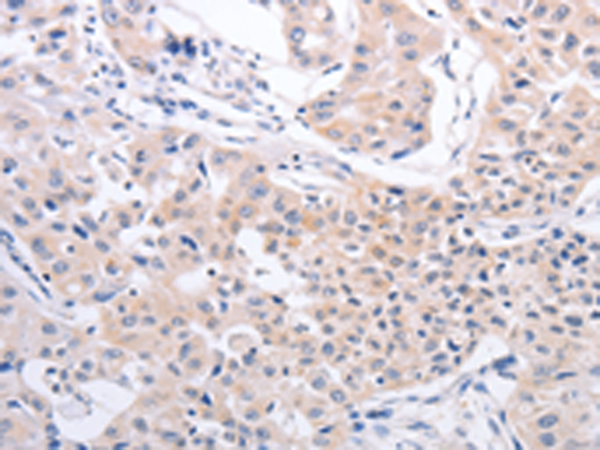

分类: 科研抗体货号: P07553别名:应用: IHC反应种属: Human, Mouse, Rat